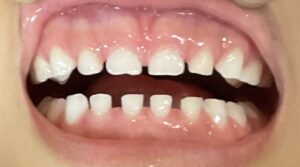

本来の正しい歯並びはすき間があることで、綺麗に並んでいるから問題ないわけではありません。

乳歯よりも永久歯の方が大きい

見出しにもある通り乳歯と永久歯ではまず大きさが違います。

特に上の前歯4本は7ミリ、下の前歯4本は5ミリ程度乳歯よりも大きいです。

大きさが違うのに乳歯が生えていた場所に無理やり歯が生えてきたらどうなると思いますか?

そうです。横に生えてきたり、前後に生えてきたりいわゆる叢生になってしまいますね。

これがすき間がない歯並びが与えてしまう影響です。

「子供の歯並びはすきっ歯が正解」ですので、綺麗に並んでいる場合は一度歯医者さんで相談してみましょう。